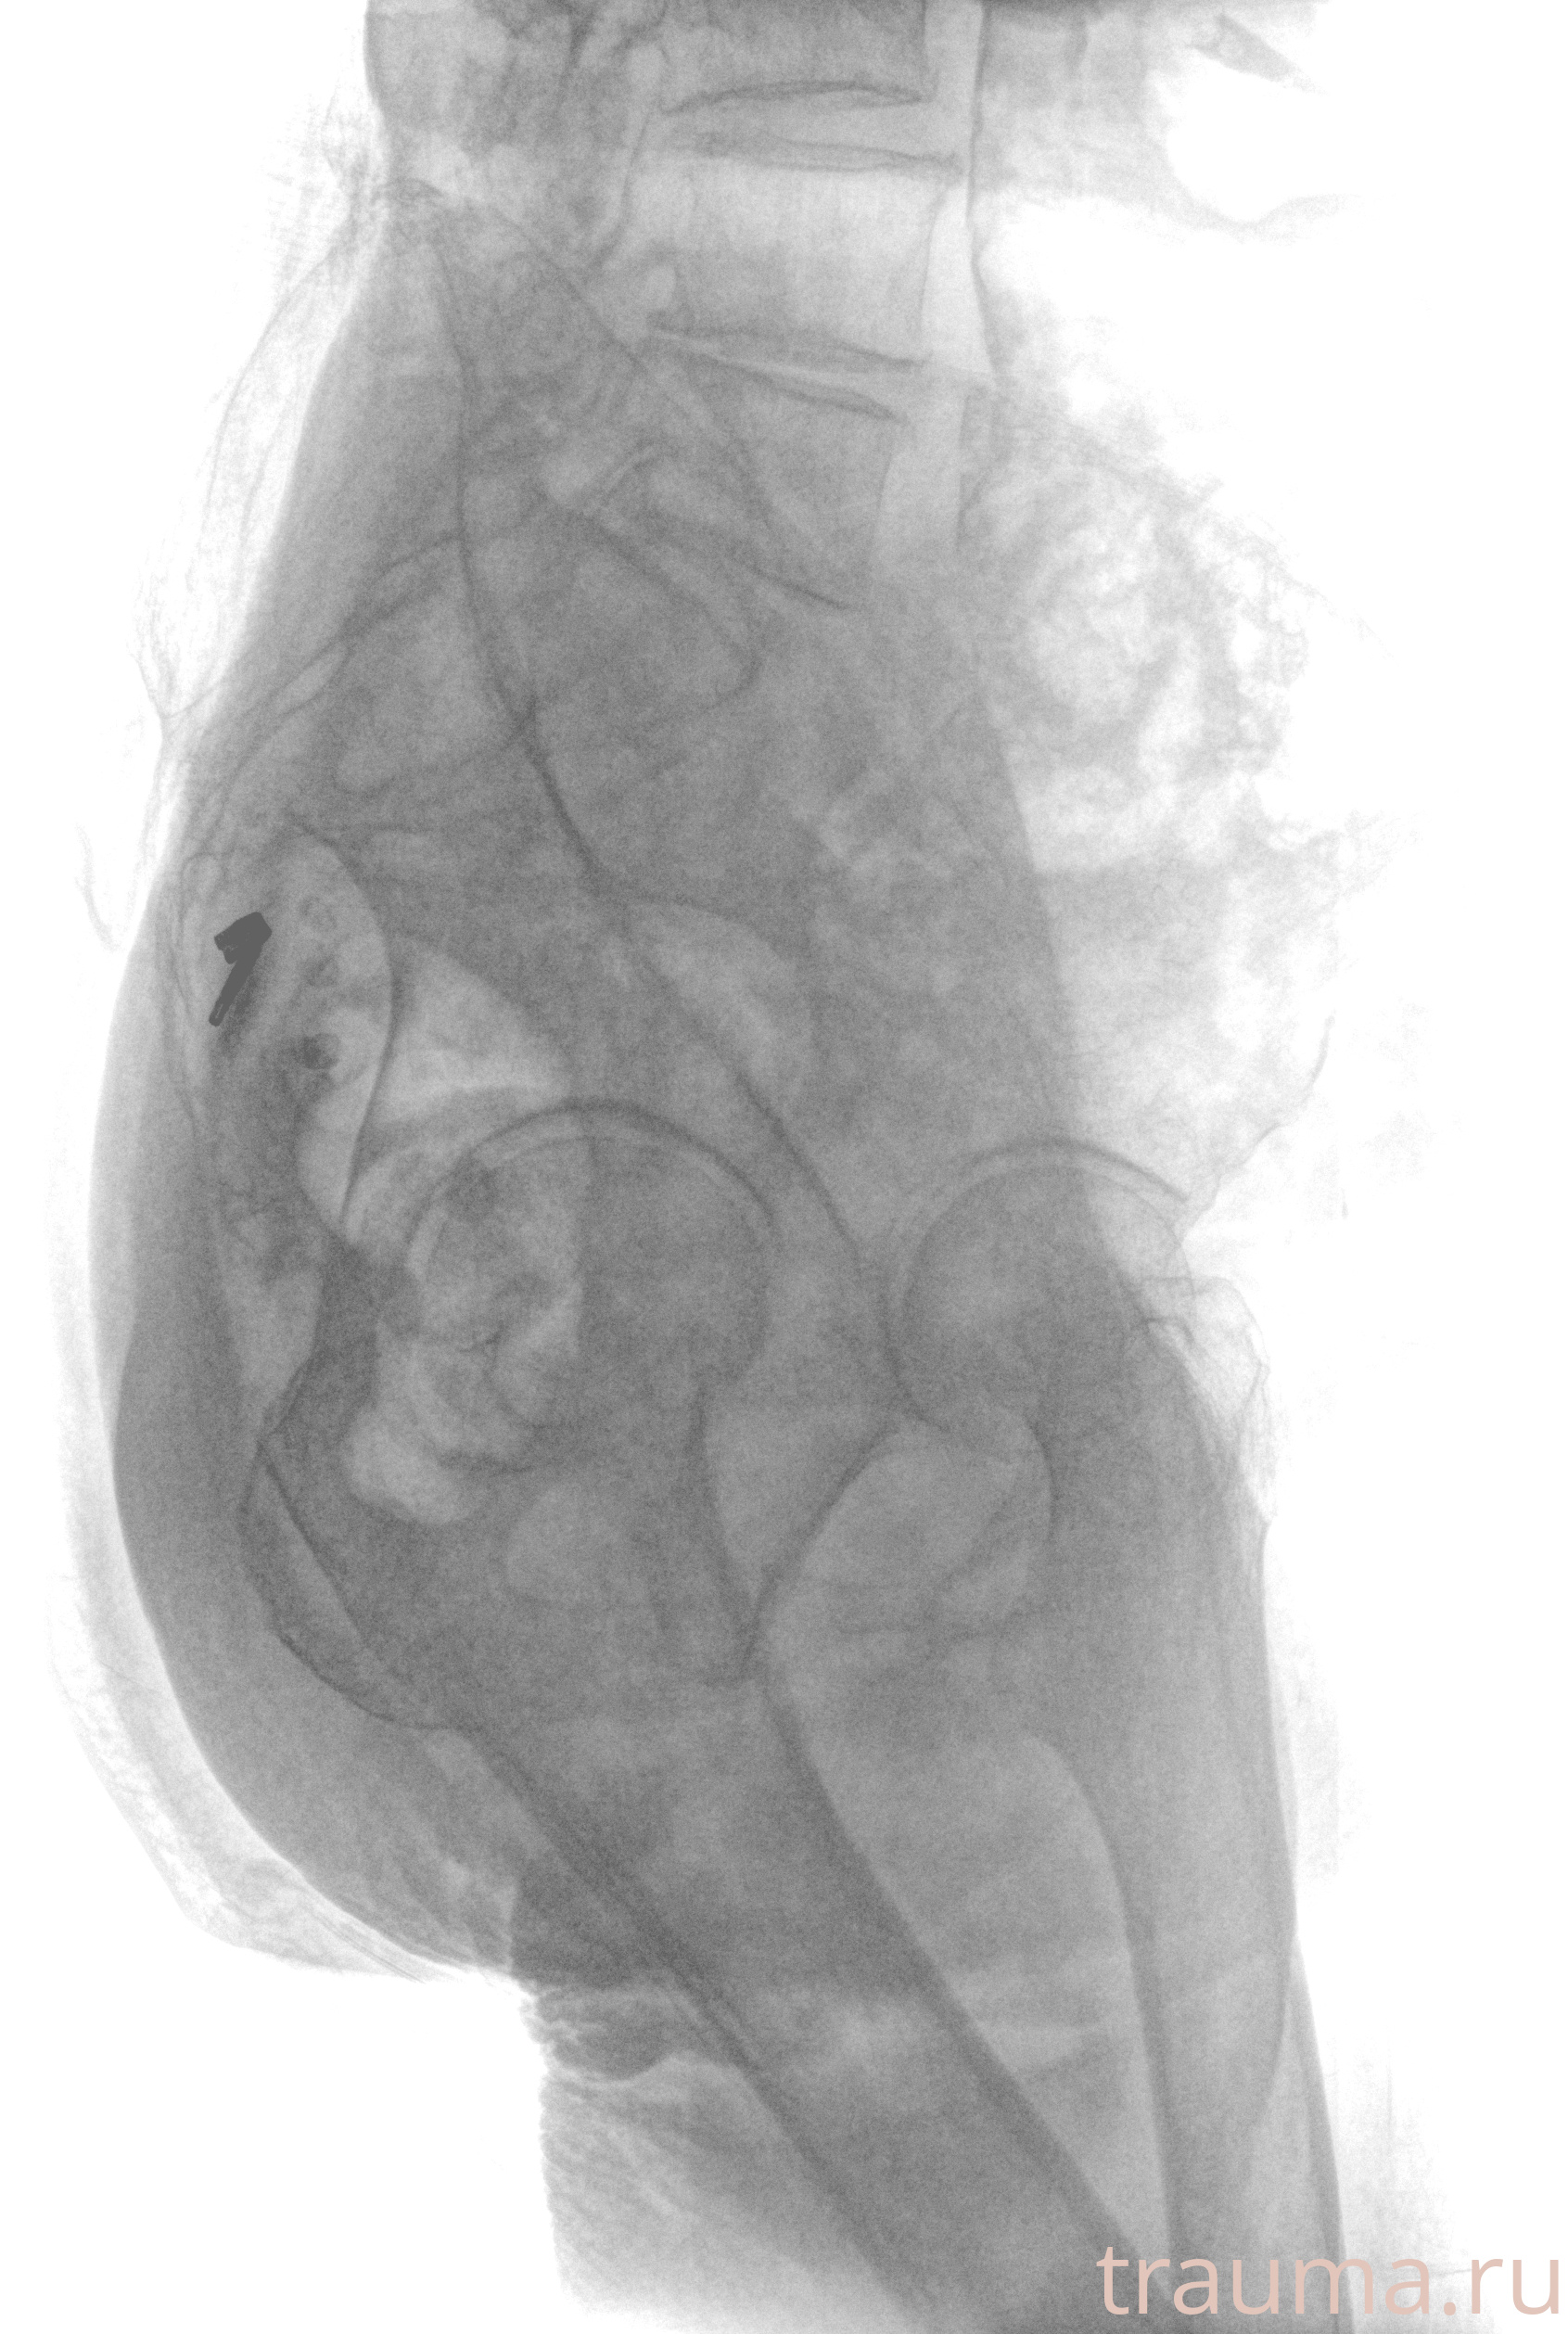

Рентген на дому: по вашему адресу приезжает врач-рентгенолог, травматолог-ортопед с мобильным рентгеновским аппаратом, проводит диагностику травмы или заболевания, делает необходимые рентгенограммы, дает рекомендации по дальнейшему лечению. Получить качественные снимки в домашних условиях возможно благодаря уникальной методике, разработанной МосРентген Центром для института  Склифосовского